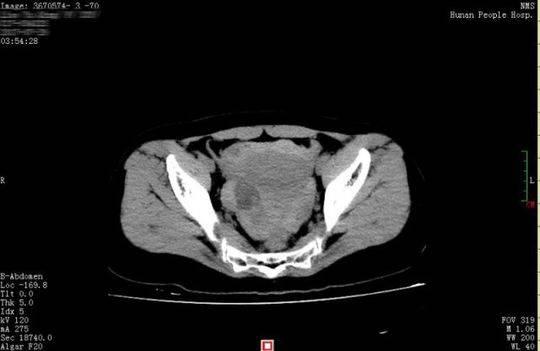

26 歲的小晴和28 歲的小東是一對新婚夫婦,因工作的緣故兩地分居。8 月16 日,近半年未見丈夫的小晴回到長沙。晚上,小別勝新婚的兩人免不了親熱一番。誰知激情過后,小晴出現(xiàn)下腹部疼痛,而且越痛越厲害,只得來到湖南省人民醫(yī)院天興閣院區(qū)急診科就診。尿妊娩檢查結(jié)果為陰性,而腹部CT 提示盆腔、腹腔有大量積血、積液,隨即轉(zhuǎn)入婦科。黃薇副主任醫(yī)師接診后發(fā)現(xiàn),小晴面色蒼白,渾身大汗淋漓,脈搏為102 次/ 分,呼吸22 次/ 分,血壓89/54mmgH, 血紅蛋白為79g/l, 已達(dá)到失血性休克的標(biāo)準(zhǔn)。

黃薇立即為小晴進(jìn)行診斷性腹腔鏡手術(shù),術(shù)中發(fā)現(xiàn)腹腔內(nèi)積血約1500ml,接近她全身總血量的40%," 再晚一點(diǎn)來,就會危及生命了"。醫(yī)生還發(fā)現(xiàn),在她右側(cè)卵巢有一個(gè)直徑3cm 左右的黃體囊腫表面有破口,破口有血塊附著,還有活動(dòng)性出血。黃薇立即為她施行黃體囊腫剝除和創(chuàng)面縫合止血手術(shù),恢復(fù)了卵巢的正常形態(tài)。